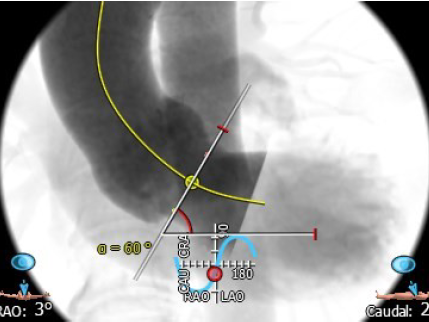

4.术中造影角度RAO:13°,CAU:14°;

主动脉与左心室夹角:127°

主动脉瓣环平面水平夹角:60°